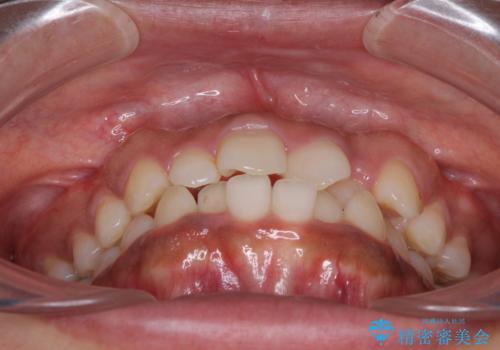

- 上下前歯の叢生を気にして来院された患者様です。

当初はインビザラインにて治療を開始しましたが、自己管理による治療が難しくなり、ワイヤー矯正へ転換して継続しました。

2年ほどインビザライン矯正を続けましたが、終了することができず、ワイヤーへ転換後は1年弱で終えることができました。